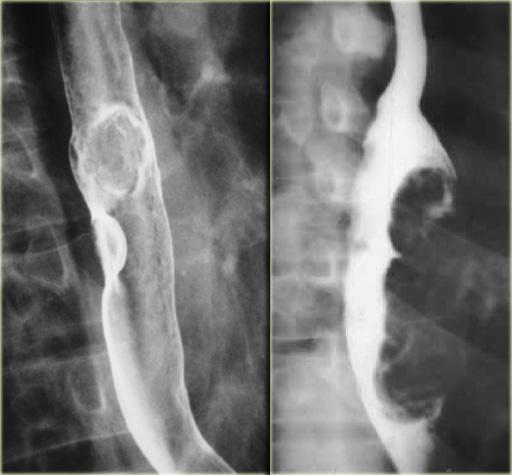

Hình bên trái là bệnh nhân không có triệu chứng với u cơ trơn thực quản.

Trên phim ngực thẳng, quan sát thấy một đám mờ bất thường phía sau tim (mũi tên).

Hình chụp thực quản cản quang barium cho thấy một khối có múi (mũi tên) không gây tắc nghẽn mặc dù kích thước lớn.

Các tổn thương niêm mạc được nhận biết qua hình ảnh bề mặt niêm mạc không đều.

Các tổn thương trong thành dưới niêm mạc tạo ra các khuyết thuốc có bờ nhẵn, và khi nhìn nghiêng, bờ tổn thương thường tạo thành góc gần vuông với thành thực quản.

Trên phim X-quang, khối u (mũi tên) lồi vào ngách azygô-thực quản.

Trên hình chụp thực quản cản quang, bờ dưới của tổn thương trong thành này tạo thành góc gần vuông (mũi tên) với thành thực quản.

Một khối thực quản có vôi hóa hầu như luôn luôn là u cơ trơn.

Hình bên trái là bệnh nhân có tổn thương thực quản vôi hóa (mũi tên) lồi vào ngách azygô-thực quản trên phim X-quang.

Tổn thương (mũi tên) trên CT và phim X-quang bệnh phẩm phẫu thuật cho thấy hình ảnh vôi hóa.

Hình bên trái là bệnh nhân với u nguyên bào cơ dạng hạt (granular cell myoblastoma), một loại khối u lành tính hiếm gặp.

Hai tổn thương này (mũi tên) có hình ảnh không đặc hiệu, tuy nhiên tổn thương ở phía gần hơn cho thấy bờ nhô ra và góc vuông, gợi ý vị trí trong thành thực quản.